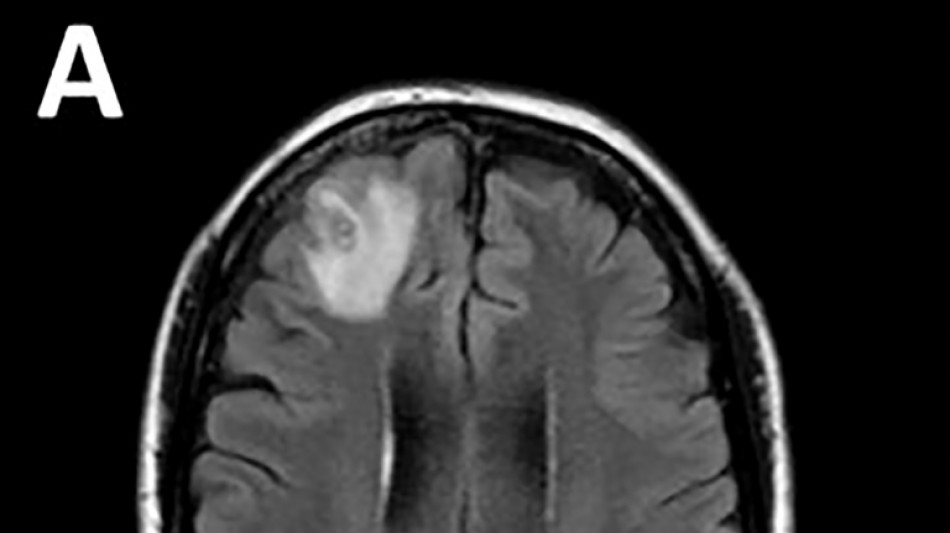

Un ver qui parasite les serpents découvert dans le cerveau d'une Australienne / Photo: © Université nationale australienne/AFP

Les médecins ont découvert une "lésion atypique", grâce à un examen IRM, dans la partie frontale du cerveau de l'Australienne, âgée de 64 ans, qui souffrait de pertes de mémoire.

Le parasite, dont la "structure en forme de fil" est apparue sur les scanners cérébraux, a ensuite été identifié grâce à des tests ADN.